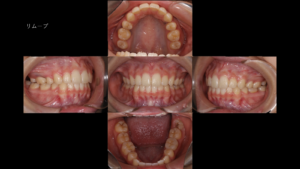

治療の結果:美しさと健康の共存

治療の結果、前歯の突出感は解消され、口元は自然で美しいラインへと整いました。 特に笑った時の印象がものすごく明るくなり、患者さんからも「自分の歯でここまで変われるなんて」と言われました。最初に書いたように、周りも幸せにできて歯科医師として良い仕事をしたなと思っています。

その結果、口元の突出感が改善し、横顔の印象も自然で調和のとれたラインへと変化しました。本人と親御さんからも喜びの声を頂き、僕もとても嬉しかったことを覚えています。 矯正治療は、その人の人生にも大きく関わることなんだなと身をもって体験しました。 正直、この経験から矯正治療がとても好きになりました。